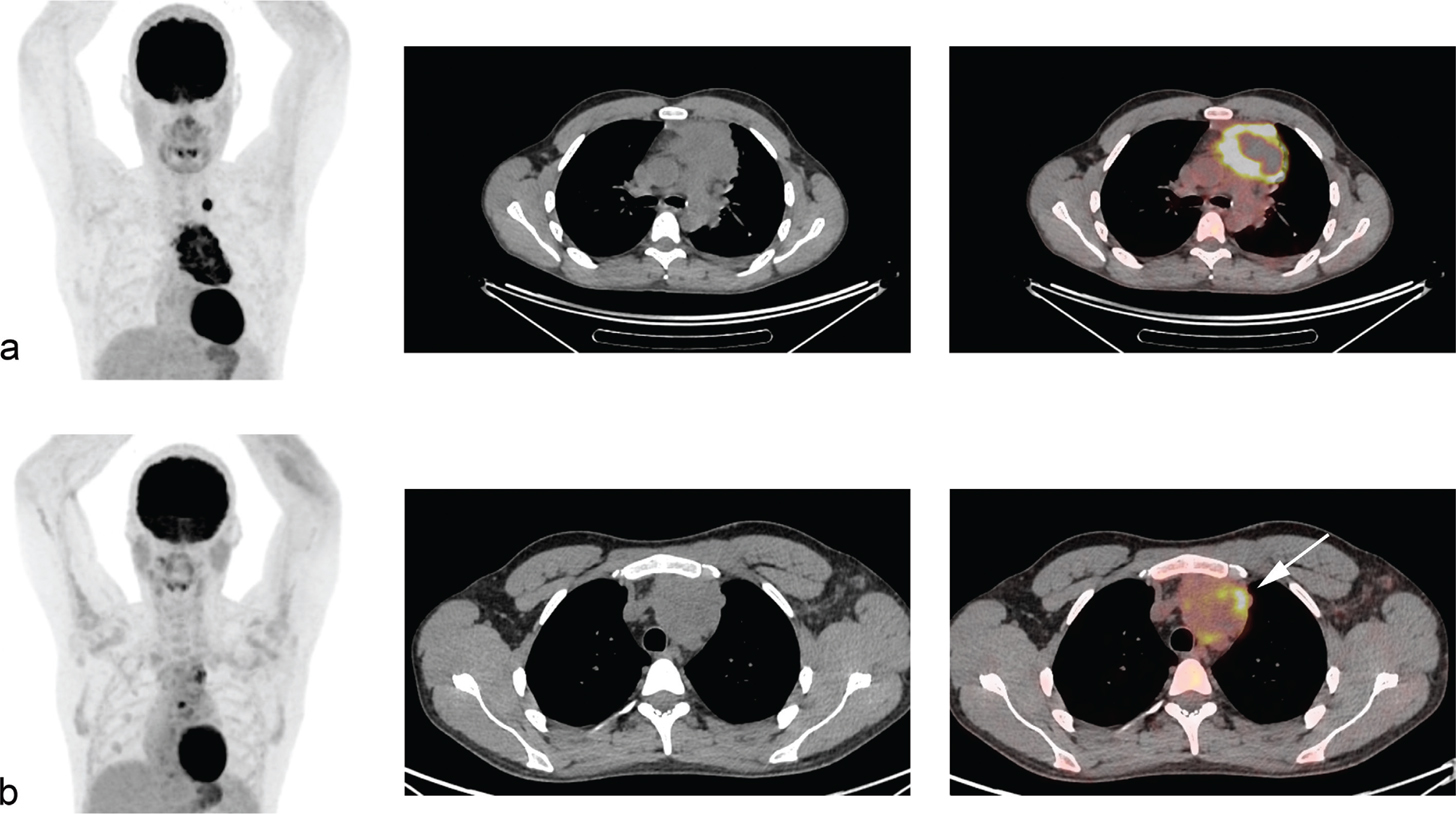

Fig 3

Figure 3. A young woman with Hodgkin lymphoma, stage II. Baseline FDG PET/CT (a). Interim PET/CT (b) performed after two cycles of ABVD (doxorubicin, bleomycin, vinblastine, and dacarbazine,) revealed partial metabolic response with residual FDG-uptake above liver uptake (lymphoma SUVmax=8.6, liver SUVmax=2), classified as DS 4.

A common language for assessing metabolic response by PET/CT is necessary to ensure that the treatment decisions are reproducible. The international harmonization criteria from 2007 proposed a dichotomous scoring system where mediastinal blood pool activity was recommended as the reference background activity to define PET positivity for a residual mass greater or equal to 2 cm in greatest transverse diameter, whereas background update was to be used for assessment of smaller lesions (28). However, dichotomous scores in lymphoma proved suboptimal. Response-adapted treatment strategies based on interim PET/CT should enable tailoring the risk of false positive/false negative assessments to the question being asked in the trial, which can be done using more granular response reporting (29). The Deauville 5-point score (DS) is now the standard for reporting PET/CT response assessment in lymphoma (Figure 2 and 3) (7). DS was conceived to graduate the intensity of 18F-Fluoro-deoxy-glucose (FDG) uptake in previously identified lymphoma lesions relative to the liver uptake. DS 1 and 2 represent a FDG uptake lower than that of liver, uptake DS 3 represents an intensity of uptake up to that of liver, and DS 4 and 5 represent different degrees of FDG uptake above liver level and new lesions (score 5) (7). For interim and end-of-therapy response assessment in HL, a scores between 1 and 3 are conventionally considered as complete metabolic response (Figure 2) whereas DS 4 or 5 represent active HL (Figure 3) (7). Several studies have shown that the Deauville score is high prognostic in HL using DS 1–3 to define a complete metabolic response (CMR) and DS 4–5 as non-response. In two recently finalized trials of PET-guided de-escalation strategies (HD16 and D18) conducted by the German Hodgkin Study Group, the trials were designed to use DS 1–2 (above the mediastinum) as negative (or equivalent), but further analyses of these trials showed that residual uptake above liver level (DS 4–5) was better in predicting outcomes (3032). In the HD16, 5-year PFS was 93.2% among PET-2-negative patients and 88.4% in PET-2-positive patients (P = .047) when using DS3+ as definition of a positive PET/CT, but when using liver cutoff (DS 4+) for PET-2 positivity, 5-year PFS was 93.1% for PET negative patients vs 80.9% for PET positive patients (P = .0011) (30). In post-hoc analyses of HD18, DS4 was the only risk factor for inferior overall survival in a cohort of patients with DS 1–4 after two cycles of BEACOPP escalated after adjustments for other risk factors (32). The timing of interim PET/CT in HL is conventionally after two courses of chemotherapy, but a negative PET/CT after 1 cycle also has a very high negative predictive value (2-year PFS 98%) and is currently used in clinical trials of very early PET/CT adapted treatment strategies (NCT03517137) (33).